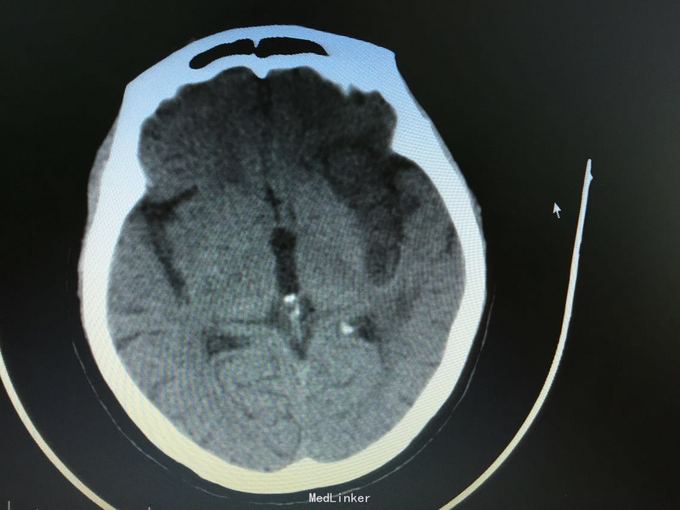

主诉:突发左侧肢体无力伴意识障碍2.5小时。 现病史:患者于2.5小时前突发左侧肢体无力,左侧肢体完全不能动,伴有意识障碍,急诊头CT显示多发脑梗死,为进一步诊治入院。 既往史:高血压,冠心病支架后,阵发房颤。

昏睡,完全混合性失语,双眼向左侧凝视,右侧肢体肌力0级,右侧病理征阳性。 头CT见多发陈旧小梗死。

目前住院10余天,意识清楚,但仍遗留左侧肢体肌力0级,混合性失语等严重功能残疾。复查CT显示为左侧大脑半球大面积脑梗死。 讨论:对于高龄,大面积脑梗死患者,时间窗内是否溶栓?静脉还是动脉溶栓?